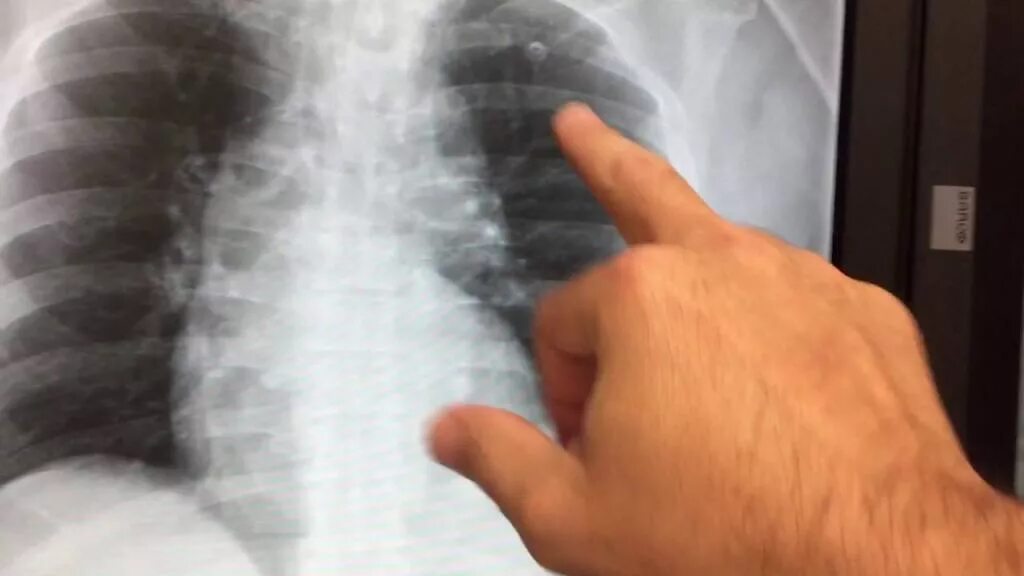

Как определить перелом ребра или ушиб